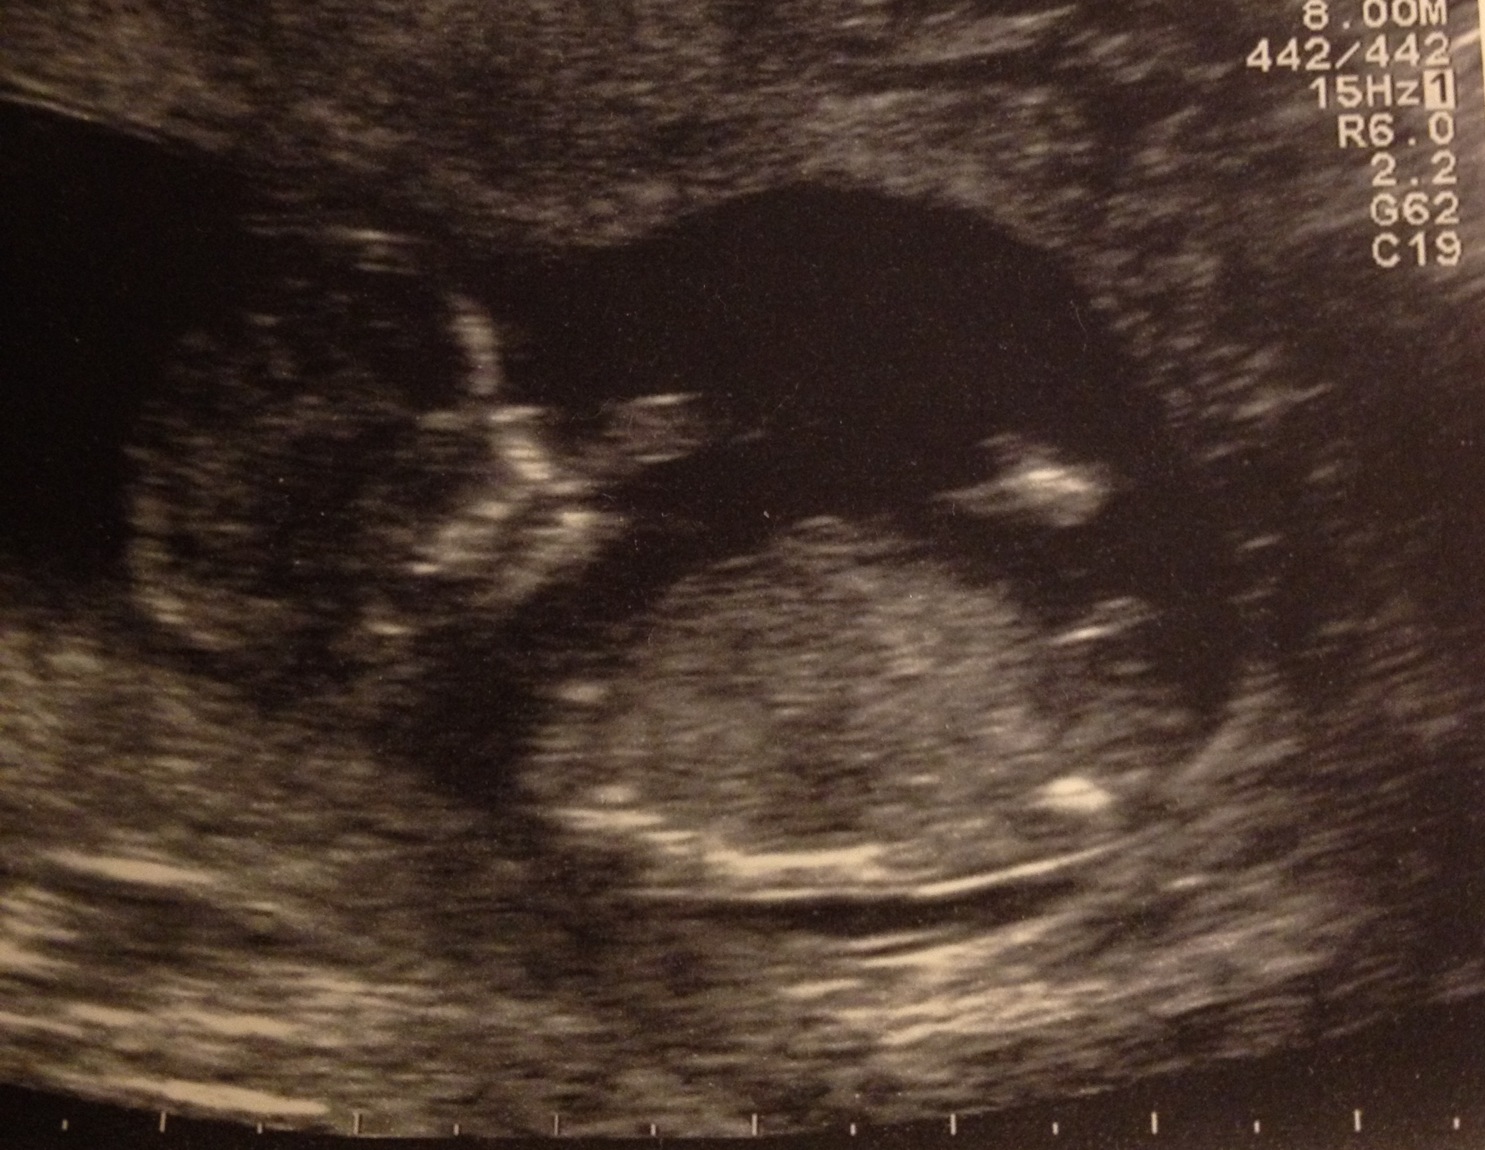

Looking boy to me

looks like a boy to me

maybe a boy

Looks like a boy! It's amazing how different nubs can look. This one looks different than the other pic you posted.